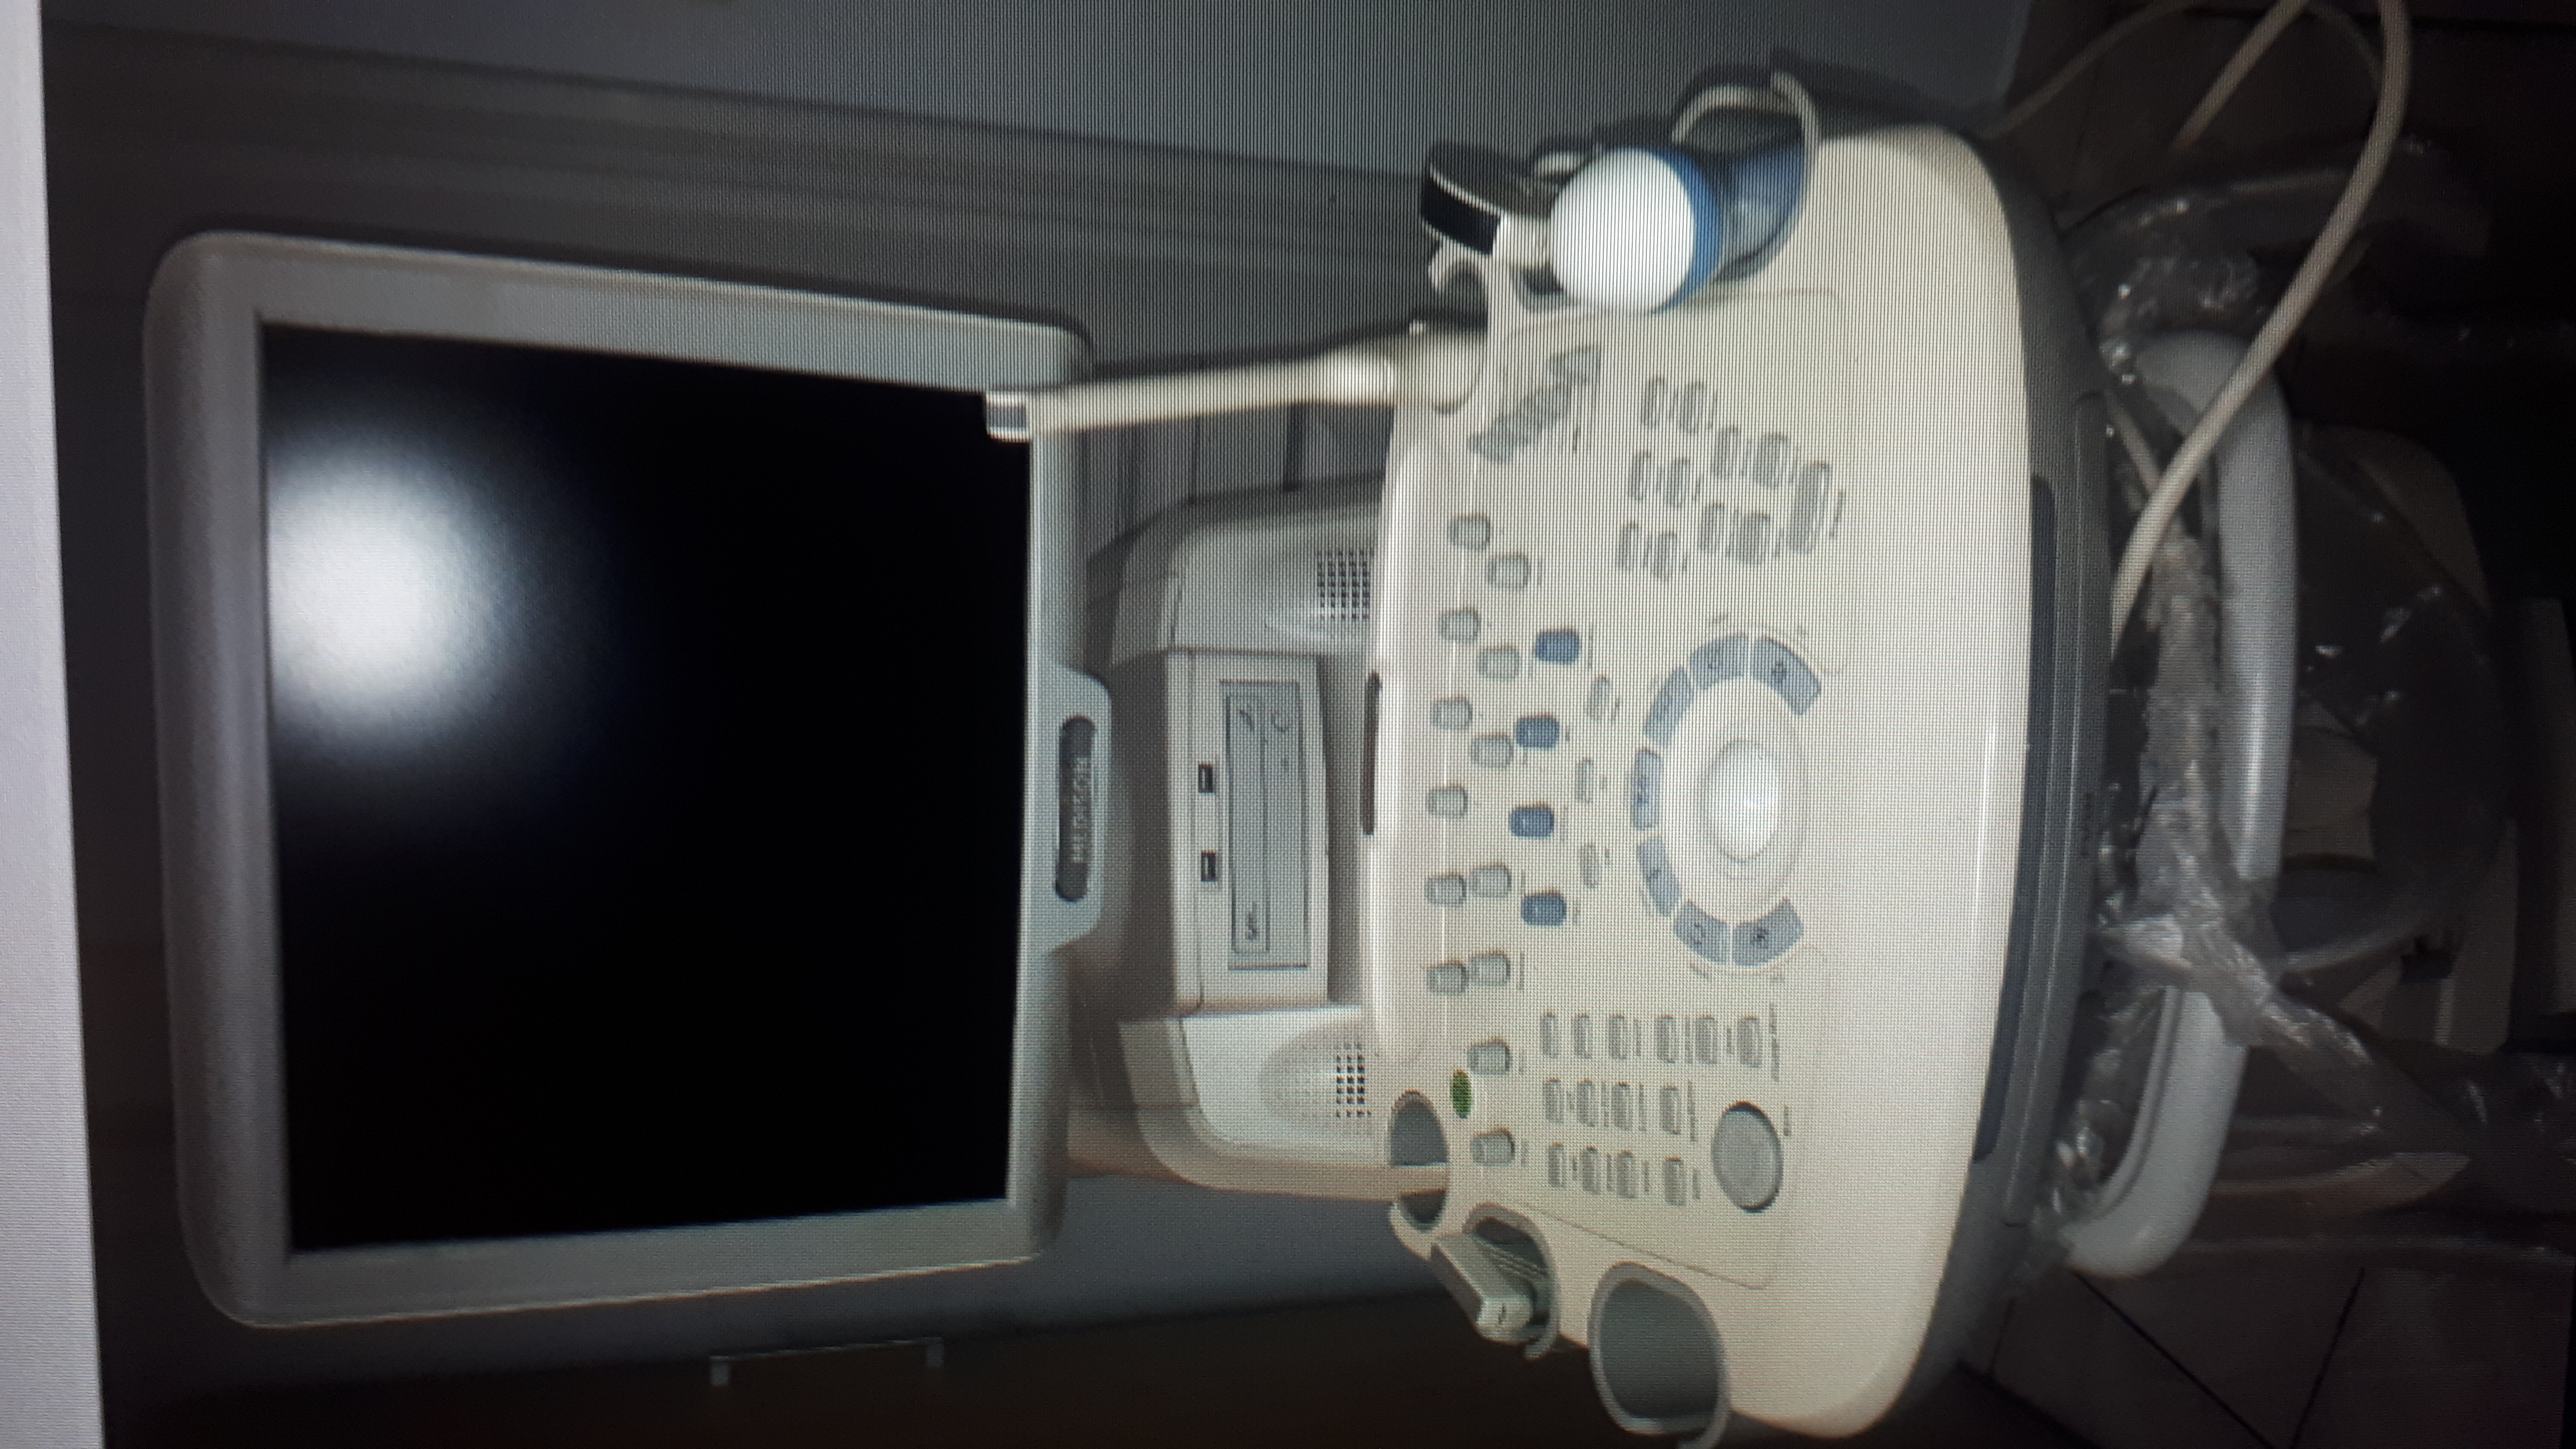

Posiadam do sprzedaży Aparat MEDISON SONOACE X8 z 4 sondami convex, endowaginalną, volumetryczną i liniową. Z funkcją Collor Doppler,Power Doppler ,Doppler pulsacyjny, z wbudowanym printerem Mitsubishi , Dodatkowo wgrany program kardiologiczny oraz pokrowiec i papierowa instrukcja obslugi : pełna

Rok produkcji 11.2007. Użytkowany od 2008 roku, 2x w tygodniu w prywatnym gabinecie ginekologicznym.